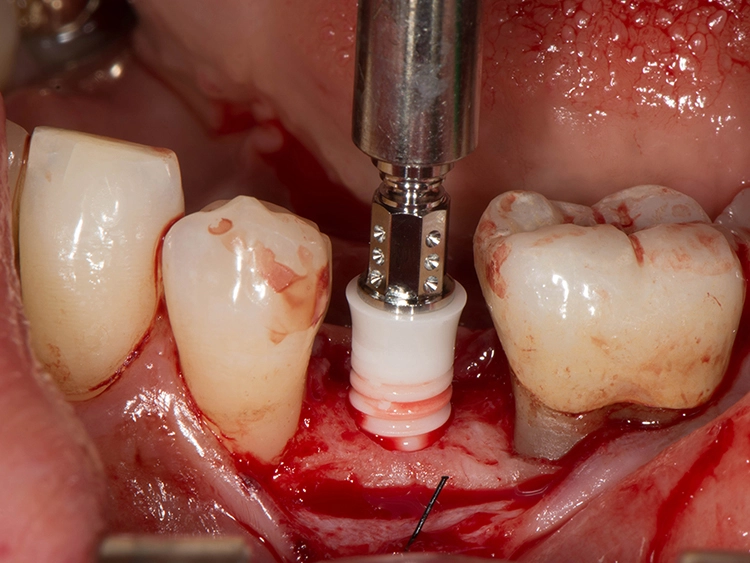

Sie bieten Vorteile, „wenn gleichzeitig eine Knochenaugmentation geplant ist und das Implantat nicht mit einer hohen Primärstabilität inseriert werden kann. Das kann im Frontzahnbereich sein, wenn eine laterale Knochenaugmentation erfolgen soll. Das gilt aber ebenso für den Seitenzahnbereich, wenn gleichzeitig ein Sinuslift durchgeführt wird, wo wir Höhe aufbauen und wir eine unerwartete Überbelastung verhindern wollen“, beschreibt der erfahrene Oralchirurg und erklärt: „Dann sind zweiteilige Implantate einfacher in der Anwendung, weil das Abutment nicht in die Mundhöhle hineinragt und daher eine ungewollte frühzeitige Belastung verhindert werden kann. Außerdem stellen zweiteilige Implantate bei zahnlosen Patienten eine verlässliche Option dar.“

Zweiteilige Implantatsysteme würden darüber hinaus mit einer höheren prothetischen Flexibilität punkten, weil die Aufbauten individueller gestaltet werden können. Dr. Röhling: „Das kann ein Vorteil sein, wenn etwa die prothetische Achse korrigiert werden muss.“ Hinzu kommt, dass bei Anwendung von zweiteiligen Systemen eine Zementierung, die für Fehlerquelle anfällig gesehen wird, entfällt, da sie eine reversibel verschraubte Befestigung erlauben, während bei einteiligen Implantaten die Suprakonstruktion nur zementiert gestaltet werden kann (siehe Fallbeispiel, Abbildungen 1 bis 10).